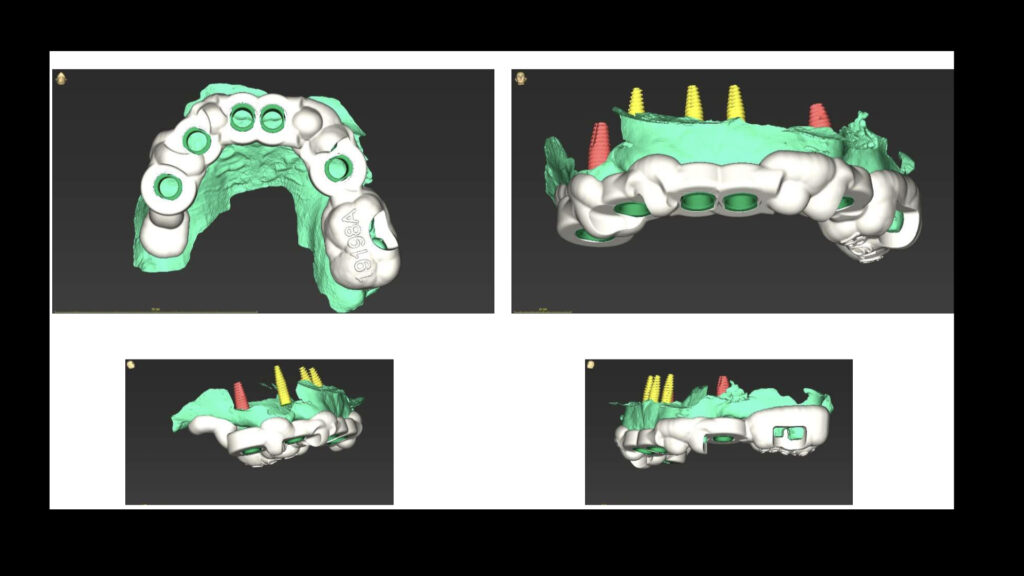

We start with detailed 3D scans and bone assessments to create a treatment roadmap just for you. - Gentle Implant Placement

A full jaw implant procedure is an advanced, multi-stage process that begins with a comprehensive consultation. At D’Amico Dental Care in Watertown and Wayland, during this initial phase, our dentist conducts thorough examinations and uses 3D imaging (CBCT) to evaluate your jawbone quality and density. Based on your specific needs, they’ll create a personalized treatment plan that determines the exact number of implants needed (typically 4-6 per jaw) and their ideal placement positions.

When considering full mouth dental implants, it’s important to understand that the final phase begins after successful osseointegration. Your dentist takes precise impressions to craft permanent prosthetics (fixed or advanced removable) in a specialized lab. Made from high-quality, durable materials, these custom prosthetics attach securely to your implants, delivering natural-looking results that function like real teeth.